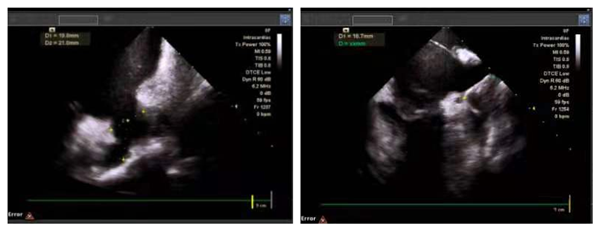

患者连某某,女,83岁,多年来饱受心房颤动的困扰,每于房颤发作时自觉胸闷、心慌显著,并且由于房颤血栓形成导致脑梗死。王洪涛教授接诊患者后,为其进行规范细致的诊疗,经判断,该患者CHADS2评分高达五分,适合进行房颤一站式手术。在进行充分的术前准备后,王洪涛教授行心腔内超声(ICE)指导下射频消融术+左心耳封堵术,历时2小时30分钟。8F超声导管经由房间隔穿刺鞘进入左房进行心耳大小测量、左心耳封堵器位置评估及释放后评估。

心腔内三维超声技术(ICE)是国际心内介入领域兴起的一项新技术。近年来,该技术越来越多应用在“一站式”手术中,使病人免除食道超声痛苦,避免全麻。心腔内超声导管通过患者的下腔静脉血管送入患者心腔内,如同术者的第三只眼睛,帮助看见心脏内解剖结构,实现更精准安全的房间隔穿刺,并且从各个角度灵活自由地评估心耳形态,帮助选择合适大小的封堵器,评估并释放。